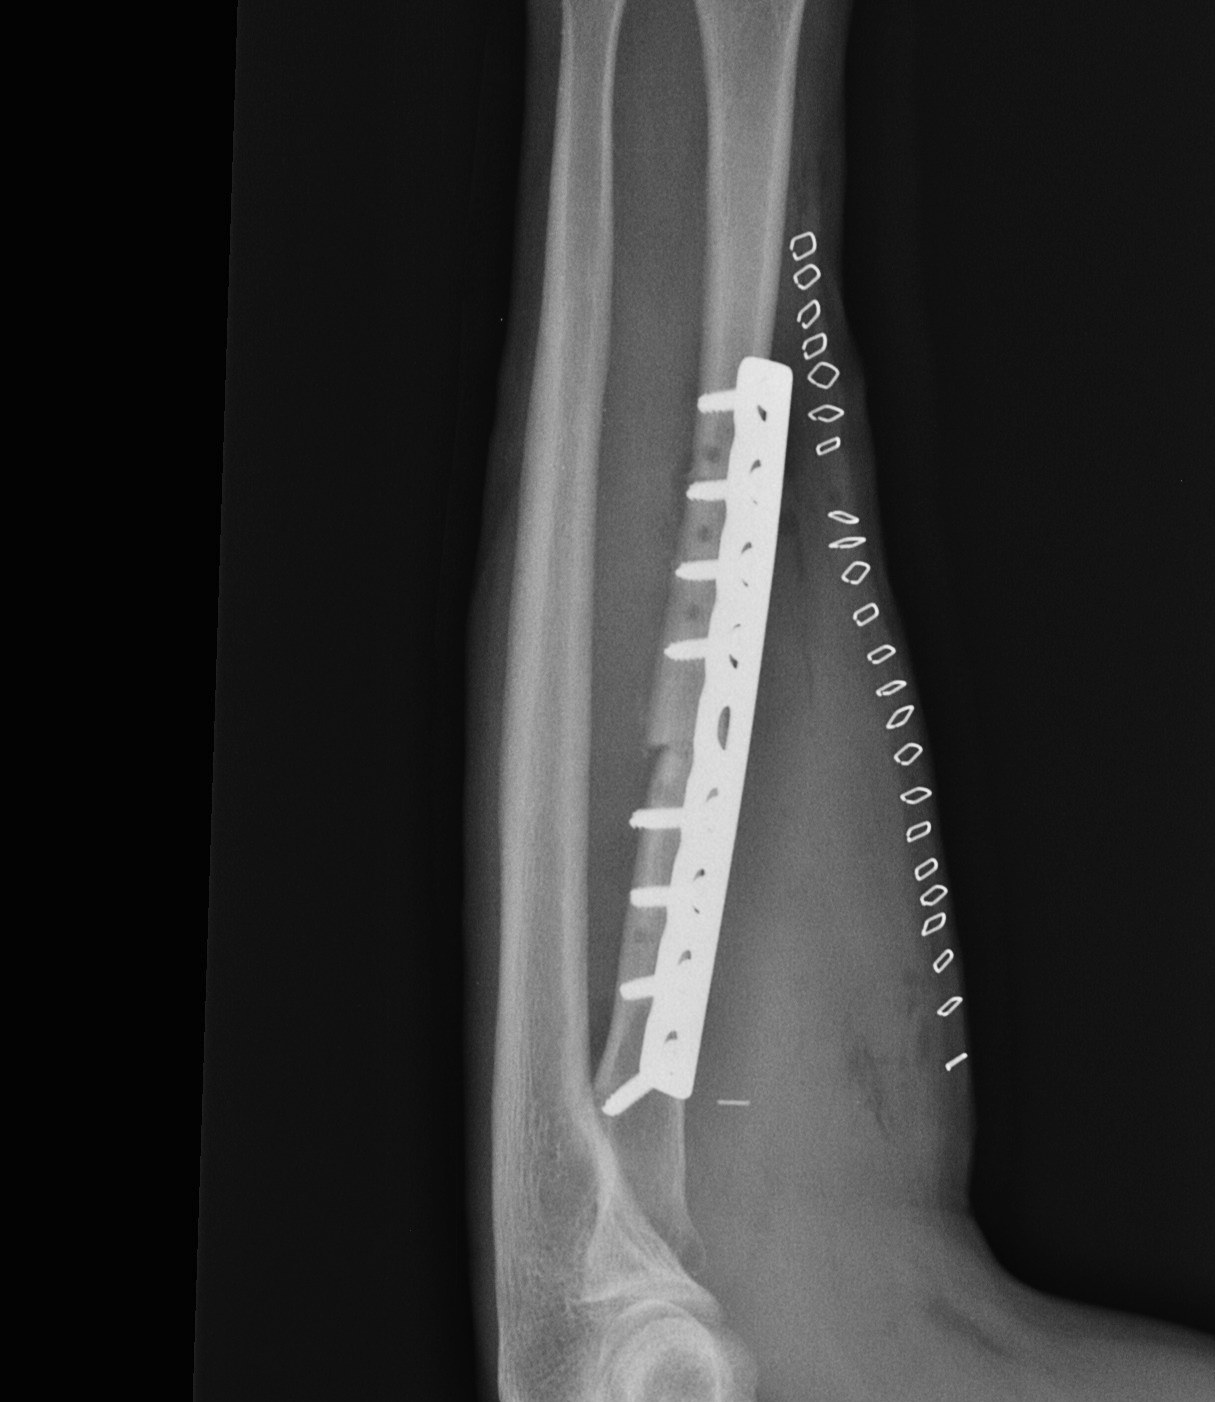

Radial fracture malunion requiring corrective osteotomy

ORIF with DCP plates

Fixation with DCP plates

Revision compression plating + drill intra-medullary canals + autograft